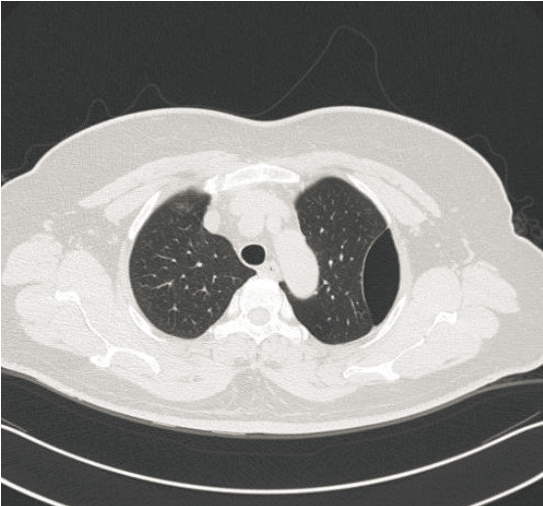

ct打印胶片怎么用远程就医、转院就医时,CT核磁DICOM电子胶片的重要性!【就医知识】_https://www.jmylbn.com_新闻资讯_第1张

(DICOM格式)